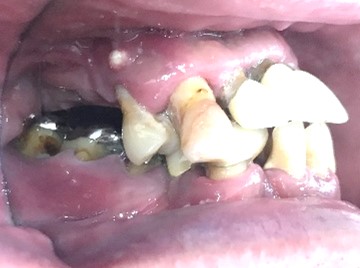

Before

赤丸は抜歯しました

After

【義歯を装着したところ】

【義歯を外したところ】

他の歯も歯周病が進行していました。保存することができない歯が3本ありましたので、抜歯し、残った歯6本の歯周病治療をし、それらの歯を活用しマグネット式総入れ歯を入れました。

所感

マグネット式総入れ歯を活用し、もともとは反対交合でしたが、正常交合に改善することができました。